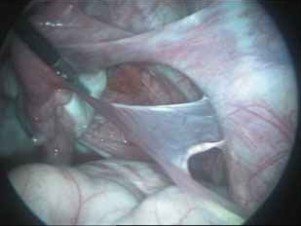

- Porción ampular, es la parte más distal de la trompa y termina en una estructura en forma de mano, llamada fimbria, que tiene unas proyecciones digitales con las que abraza al ovario en el momento de la ovulación.

A veces también el óvulo fecundado no logra llegar hasta el útero y se queda en una trompa , provocando lo que llamamos EMBARAZO ECTOPICO TUBARICO.